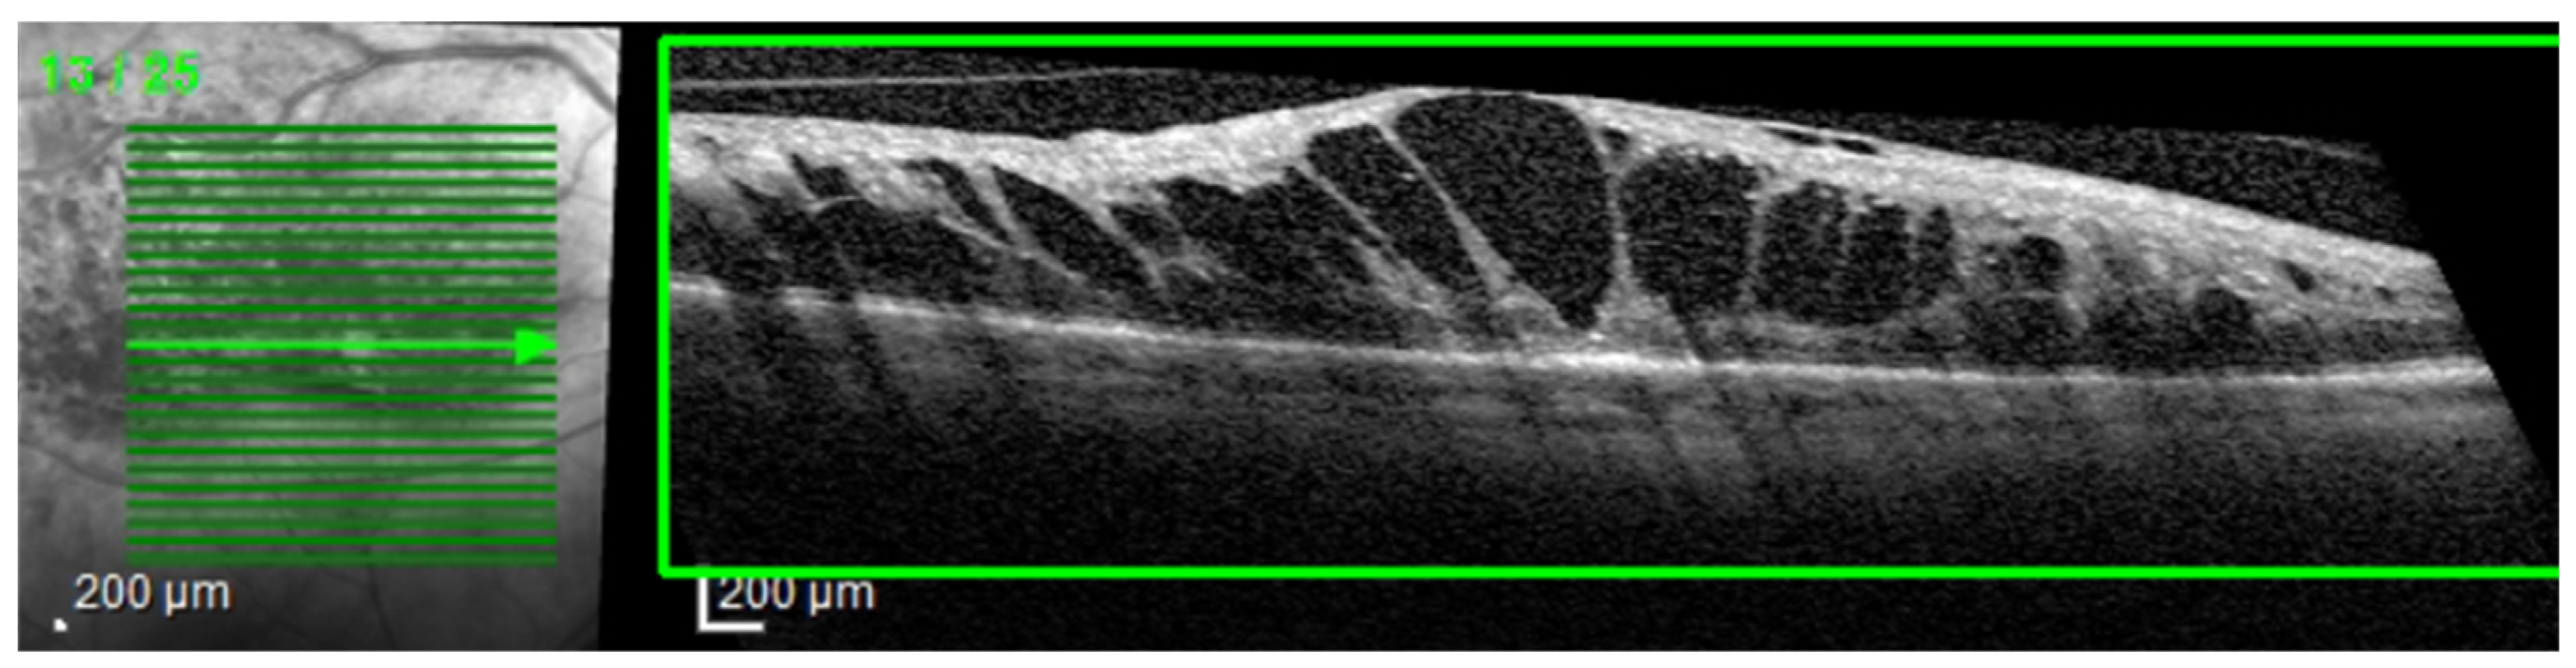

Even though our dataset contains B-scans with scan-level annotations, these scans are part of volumes. The dataset does not contain complete volumes; therefore, we call them sequences. Figure 11 presents such scans that are part of a sequence: the detachment is obvious in 114–116 scans, but less obvious in scans 117–120. From the medical perspective, we consider that a model that identifies the detachment in at least one scan from all sequences that contain a detachment is better than a model that identifies all detachment scans in one volume but completely misses the detachment in another volume. At the same time, if the model is trained using a multilabel approach, it could be possible that, for example, in a sequence of DME combined with ND and HF, the model fails to identify correctly the complete combination in all the scans, but it detects DME and ND in one scan and DME and HF in another.

Figure 11.

Scans from a sequence: ND is obvious in scans 114–117, and less obvious in scans 118–120.

The assumption of scan independence made by the common ML metrics computed at the scan level does not capture these aspects; therefore, we introduce new metrics that evaluate the model’s ability to signal the presence of biomarkers in a sequence (even though it might miss it in one scan from that sequence). Therefore, we introduce SeqAcc and SeqIoU, which are defined in the next paragraphs.

The fact that ND is very difficult to detect, for example, in scan 120 independent of the neighboring scans, and stresses also the difficulty of annotating such data. Hard examples (such as 118) could be extremely valuable for the models to learn to detect even the smallest signs of lesions.